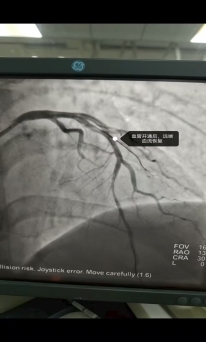

37岁的曹先生上午在家中突发剧烈胸痛、大汗淋漓,被紧急送往我院。入院后,急诊科迅速为他进行了全面检查,但心电图和早期心肌损伤标记物均为阴性,遂收入住院进一步诊治,我院心内二科黄涛医生凭借丰富的临床经验,敏锐地察觉到患者病情的严重性,果断判断这是一例不典型早期心梗。病情就是命令,时间就是生命!心内二科胸痛中心团队迅速启动绿色通道,一键激活导管室,各参与救治人员间紧密配合。在患者进入导管室后,团队凭借精湛技术,快速完成冠状动脉造影,明确患者前降支近段完全闭塞,立即实施冠脉介入治疗开通罪犯血管,仅用数分钟就恢复了前降支远段血供,为患者赢得了宝贵时间。术中血管开通后,曹先生胸痛症状随即缓解。